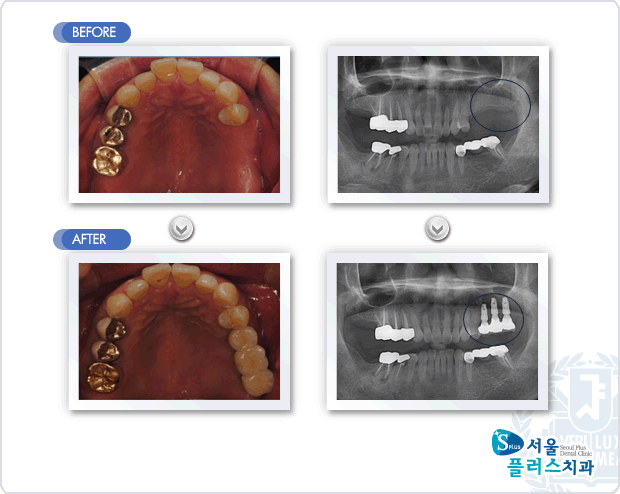

[임플란트] 상악 좌측 구치부의 치아상실